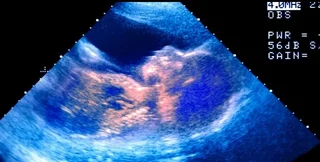

Начиная со второго триместра беременности, мама может почувствовать, как ребенок пинается и переворачивается, но может ли он плакать? С помощью ультразвука ученым удалось увидеть, как у плода, возрастом 33 недели, на лице была мимика, которая была похожа на плач. После этого ученые провели вибрационную и шумовую стимуляцию плода и заметили интересное поведение, сообщает ScienceAlert.

Во время стимуляции младенец широко открыл рот, сделал несколько выдохов и запрокинул голову, все закончилось дрожью подбородка. Подобное поведение было замечено у 10 младенцев. Был ли это плач? Все зависит от того, что вы подразумеваете под плачем, говорят ученые.

Изменения выражения лица младенца в утробе матери

Фото: ScienceAlert